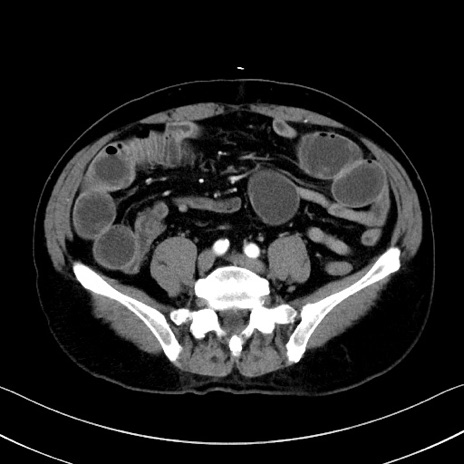

症例35(横断像)

【症例】70歳代 男性

【主訴】腹部膨満、嘔吐

【現病歴】昨日より腹部膨満感出現。本日増悪し、仙痛出現。嘔吐あり、受診。

【既往歴】糖尿病、胆摘後

【身体所見】BP 149/80mmHg、HR 74/min、BT 35.9℃、腹部:膨満、軟、圧痛なし。腸雑音減弱あり。上腹部正中切開瘢痕あり。

【データ】WBC 13500、CRP 1.72